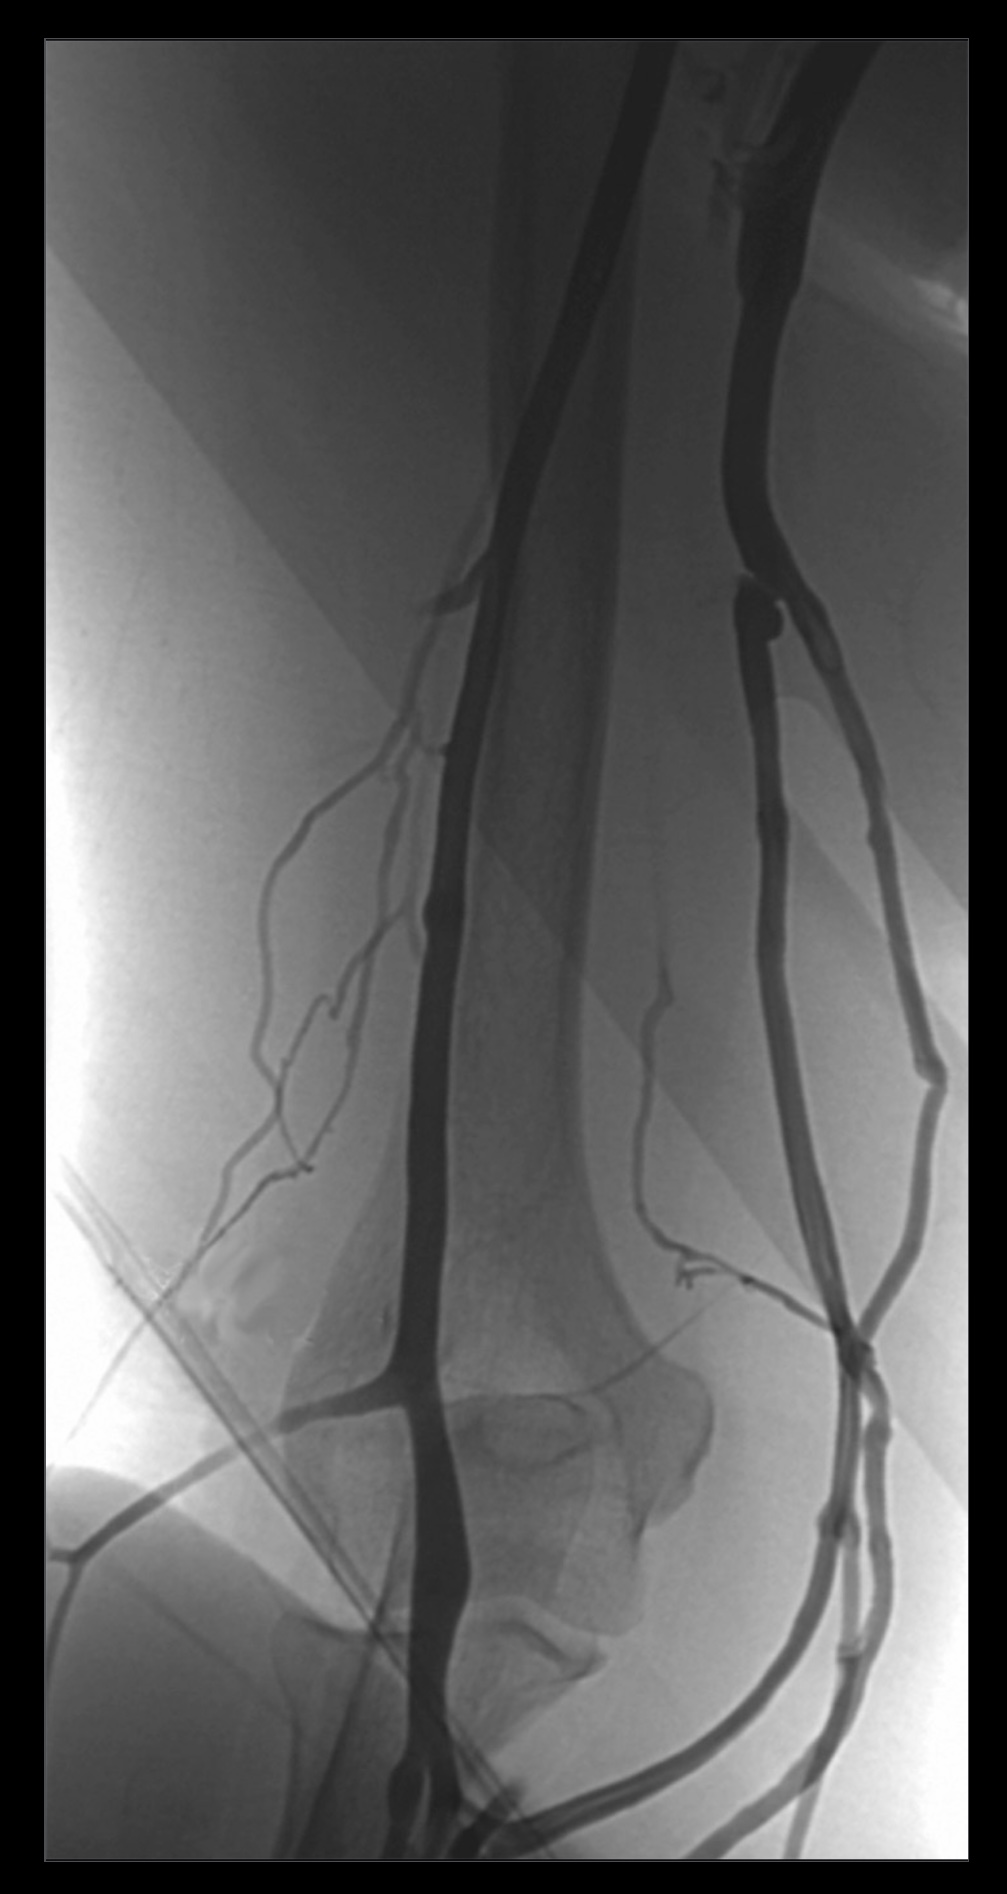

1. An 63 year old man has a heart arrhythmia. Upon further investigation, an angiogram shows an occlusion of the proximal right coronary artery. Why would this potentially cause arrhythmia? Discuss the anatomy and relationships of the right coronary artery and branches as well as the complementary venous drainage. Include mention of any commonly seen anatomical variances, if any.

2. A patient is shown to have a partial occlusion of their anterior interventricular artery (left anterior descending artery). Discuss the anatomy and relationships of the left coronary artery and branches as well as the complementary venous drainage. Why is an occlusion in this artery especially dangerous and what potential surgical solutions can be used as treatment? Include mention of commonly seen anatomical variances, if any.